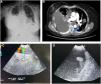

A woman, 72 years old, with a history of breast neoplasia diagnosed a year ago, treated with surgery, chemotherapy, and radiotherapy, presented to the Emergency Department with symptoms of dyspnea evolving over a few weeks. Chest X-ray showed a pleural effusion with nodular images resembling balloon releases (Fig. 1A). Further evaluation with chest computed tomography (CT) revealed mediastinal lymphadenopathy with infiltration of the inferior pulmonary vein (Fig. 1B). Subsequently, diagnostic endobronchial ultrasound (EBUS) was performed, revealing an implant at the level of the inferior pulmonary vein and left atrium (Fig. 1C and D). Anticoagulant therapy was initiated based on these findings. The histological diagnosis was breast carcinoma.

(A) Postero-lateral chest X-ray showing right pleural effusion along with contralateral nodular images. (B) Axial CT scan of the chest demonstrating pleural effusion along with an adenopathy cluster infiltrating the inferior pulmonary vein (arrow) and contralateral nodule. (C) Doppler ultrasound image at the level of the pulmonary vein showing an endoluminal vascular lesion with Doppler signal around it. (D) Ultrasound image revealing an implant at the level of the left cardiac cavity.